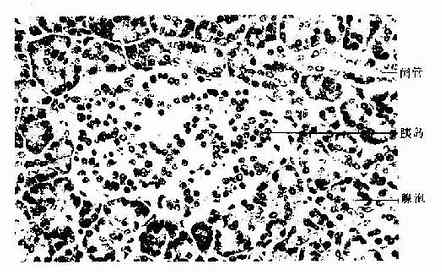

胰腺表面覆以薄层结缔组织被膜,结缔组织伸入腺内将实质分隔为许多小叶,但人胰腺小叶分界不明显。腺实质由外分泌部和内分泌部两部分组成。外分泌部分泌胰液,含有多种消化酶,经导管排入十二指肠,在食物消化中起重要作用。内分泌部是散在于外分泌部之间的细胞团,称胰岛,它分泌的激素进入血液或淋巴,主要参与调节碳水化合物的代谢(图13-4)。

图13-4 人胰腺 HE×400

胰岛(pancreas islet)是由内分泌细胞组成的细胞团,分布于腺泡之间在(图13-4)。成人胰腺约100万个胰岛,约占胰腺体积的1.5%左右,胰尾部的胰岛较多。胰岛大小不一,小的仅由10多个细胞组成,大的有数百个细胞,也可见单个细胞散在于腺泡之间,胰岛细胞呈团索状分布,细胞间有丰富的有孔型毛细血管,细胞释放激素入血。人胰岛主要有A、B、D、PP四种细胞,某些动物的胰岛内还有D1细胞、C细胞等,细胞之间有紧密连接和缝隙连接。HE染色切片中不易区分各种细胞,一些特殊染色法可显示A、B、D三种细胞。近年多用电镜和免疫细胞化学法区分和研究胰岛各种细胞(图13-7,13-8)。